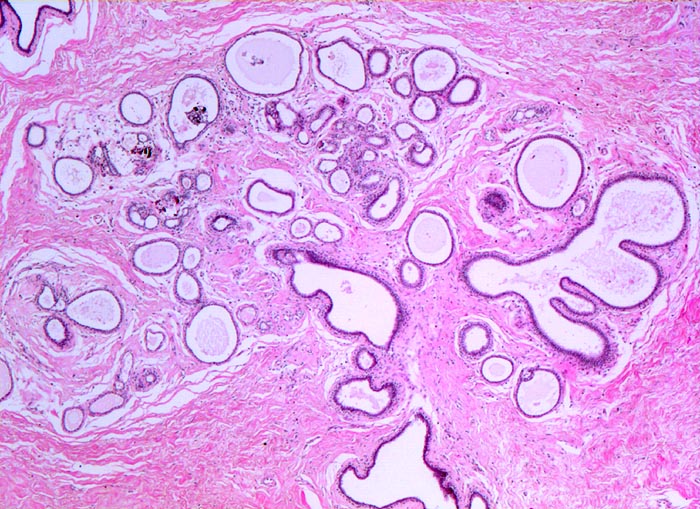

fibrös zystische Mastopathie mit intraduktalen Mikroverkalkungen

Mammagewebe mit fibrosiertem interlobulärem Stroma. Stroma der Drüsenläppchen ebenfalls fibrosiert (verdichtetes Kollagen). Die Ausführgänge sind teilweise erweitert und enthalten teilweise Mikrokalk.

Probeexzision wegen umschriebenen Mikroverkalkungen in der Screeningmammographie. Bei der Palpation lassen sich mehrere unscharf begrenzte derbe Knoten tasten.

Histologie

320